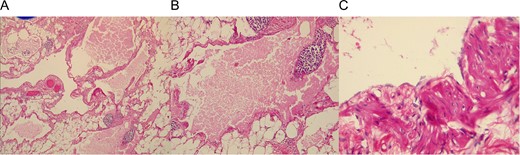

The external surface of the mass had a yellowish like-fat aspect and contained white milky fluid, the mass contained some cystic lesions and the wall was 0.5 cm in width (Fig. 1C). Pathology reported encapsulated fat tissue surrounded by dilated lymph vessels that contained lymphocytes. Immunohistochemical study for D2-40 was positive. Lymphangioma cavernous was the final diagnostic (Fig. 2A–C).

(A) Adipose tissue covering lymphatic vessels with eosinophil content. (B) Dilated lymphatic vessel with a cluster of lymphocytes. (C) Cyst epithelium.